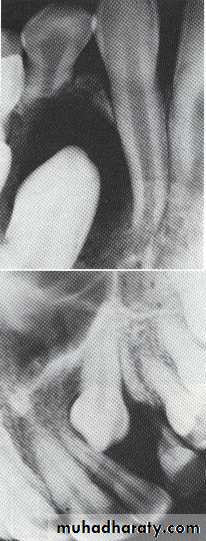

Central giant cell granuloma*A relatively uncommon, non- neoplastic mass in the jaws (intraosseous) producing an expansile radiolucent soap bubble appearance.

*Age; <20 years. Female > Male.

*Teeth are vital, with some root resorption & migration of teeth.

Multilocular appearance, expansion (arrowed) and considerable displacement of the adjacent teeth.

Buccal and lingual expansion (arrowed) and the undulating cortical border.

• Aneurysmal Bone Cyst

Large multilocular aneurysmal bone cyst

in the ramus with marked expansion andthe displacement of/8.

It is non-neoplastic ,exaggerated , localized, proliferative lesion of vascular tissue, containing giant cells.

It’s a variation of the central giant cell granuloma , can be diagnosed only by histological examination